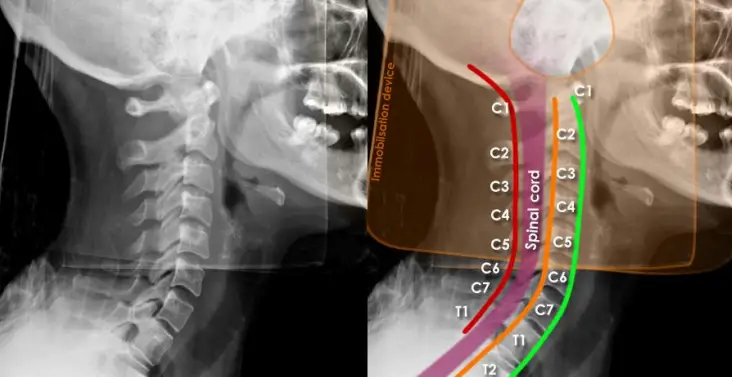

Diagnosis Methods:

Doctors use a combination of neurological exams, muscle strength assessments, MRI imaging, and electromyography (EMG) to confirm DHS.